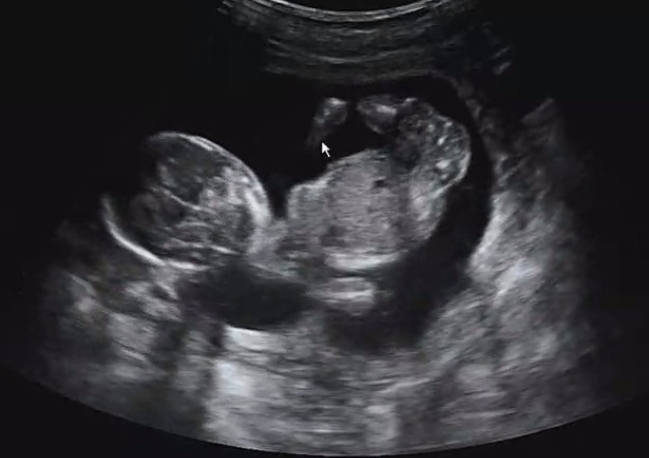

오늘로 16주 4일차라 초음파 검사로 성별을 확인할 수 있는 날이었는데요.

초음파 선생님께서 다리 사이에 고추로 추정되는 것이 보여서 거의 아들 같다고 ㅎㅎ 하셨어요!

고환 두개를 정확히 확인해야 아들로 확정을 하는데 아기 자세 때문에 정확히 보지는 못해서, 낮은 확률로 성별 반전이 나중에 있을 수도 있다고는 말씀을 하셨어요.

하지만 이 각도 저 각도에서 봤을 때 계속 고추처럼 생긴 게 보여서 주수를 고려했을 때 아마 거의 반전 없이 아들이 맞는 것 같습니다!

성별을 떠나서 주수에 맞게 잘 크고 있고 꼼지락꼼지락 잘 놀며 움직이는 모습을 보니 대견하고 흐뭇했어요.